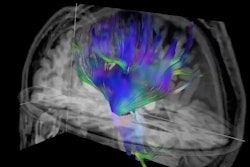

Example of structural connectivity of the three analyzed distributed cortical networks from one participant in the DIAN cohort, viewed laterally from the left (top row) and anteriorly (bottom row). Streamline colors indicate directionality of water diffusion at diffusion tensor imaging: green = anteroposterior, red = left-right, blue = superoinferior. Images and caption courtesy of the RSNA.More research on structural brain changes in people vulnerable to Alzheimer's disease is needed, wrote Linda McEvoy, PhD, of the University of California, San Diego, in an accompanying editorial.